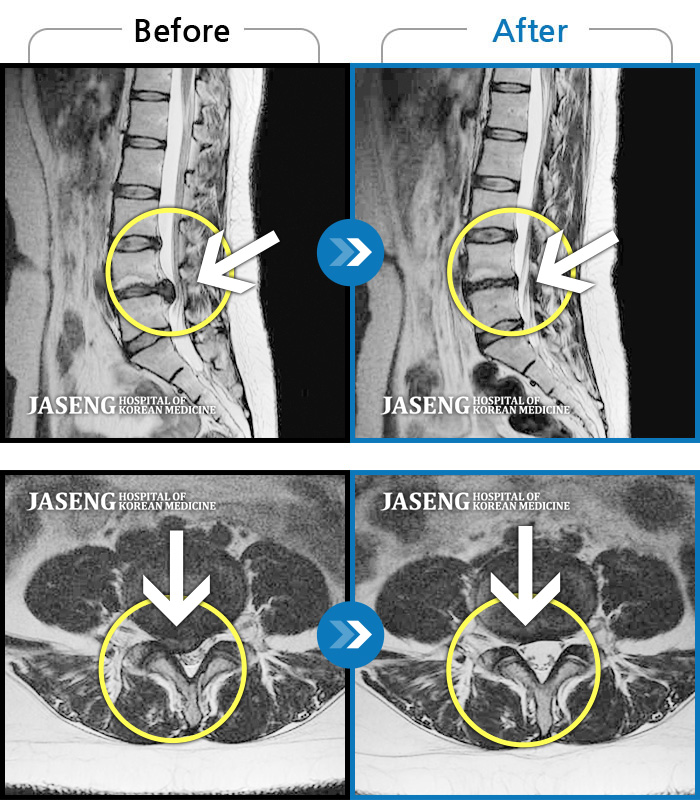

허리디스크

잠실 · 한상욱 원장

허리통증과 함께 좌측 엉치, 허벅지, 종아리 후면으로 저림이 심하여 걷기가 힘들어요.

촬영시기

2021.09.14 ~ 2022.05.14

2022.05.24